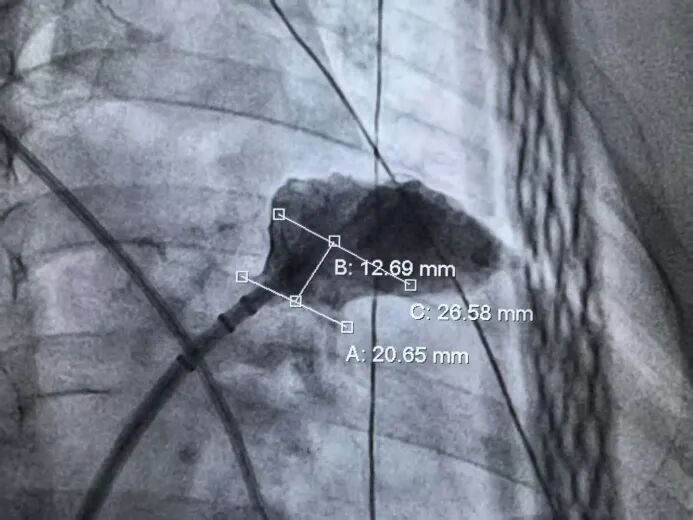

右肩位左心耳测量锚定区:26.58mm,开口区:20.65mm。

右肩位左心耳造影